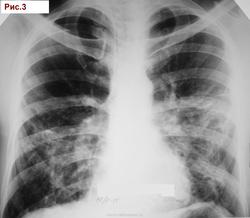

Муж.1974 г. р. Изменения впервые выявлены при проверочной флюорографии 2007 (Рис.1). Выполнена  КТ  легких (См фрагмент. Рис.2). Исчез. Продолжал работать. Не лечился. Пришел на обследование в 11.2011г. с жалобами на покашливание. Температура, кровь: норма. (Рис.3).  О какой патологии  легких можно думать? Я предположил саркоидоз. Специалистов по КТ очень прошу разъяснить рисунок 2. С уважением Nik.

Пациент обследован. Диагноз  саркоидоз органов дыхания  подтвержден. Спасибо. С уважением к Вам Nikolas